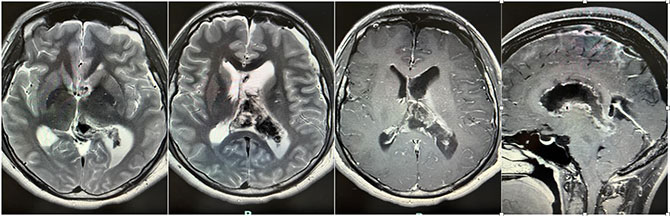

甘武副主任医师充分了解了晓敏的情况,仔细观察磁共振(MR)影像,发现肿瘤超过6cm,累及脑室多个区域,最深处已经到达后颅窝,脑干后方,肿瘤与丘脑边界不清,内部可以看到很多血管影,周围也有很多非常重要的深部静脉,涉及的都是深部中心部位的重要功能区,同时已经出现肿瘤梗阻导致的脑积水,结合肿瘤的信号特点,考虑是中枢神经细胞瘤。发现时往往已经比较大,而且合并有脑积水,正是这种肿瘤的特点。而且,手术出血多、手术创伤大、手术后出现出血、感染、偏瘫、语言和记忆功能障碍、脑积水甚至昏迷等情况并不少见。

晓敏术后出现短暂肢体乏力、语言和记忆力障碍,但很快恢复,术后第3天已能够自主活动和进食,第4天已能完全自由活动和交流。复查后显示,手术区域有少许血水,肿瘤已基本消失,切除程度超95%,脑室明显缩小,脑积水解除。病理结果显示为,中枢神经细胞瘤,和预判一致。晓敏恢复很不错,顺利出院。